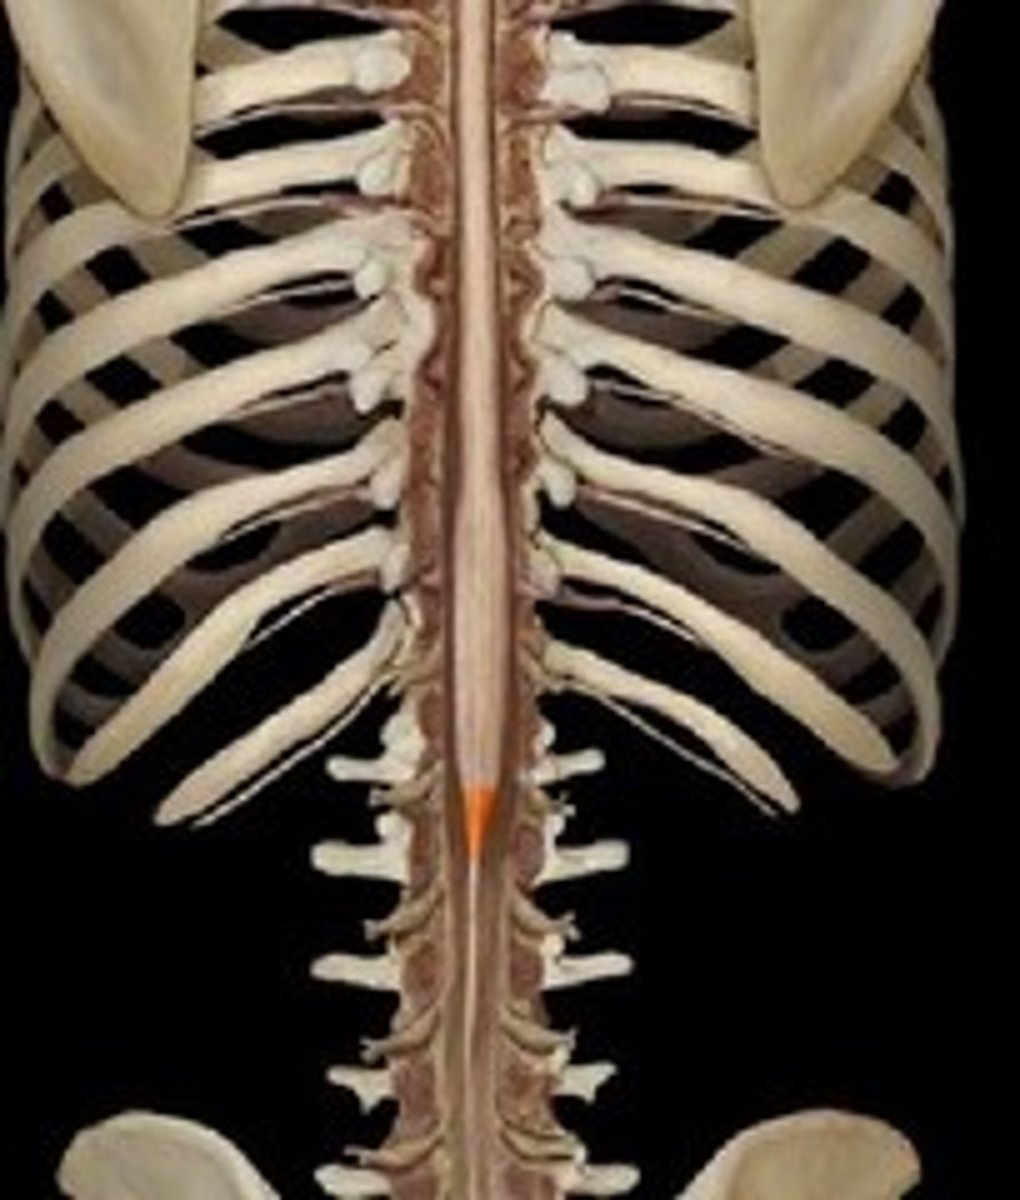

conus medullaris

filum terminale

single thin thread of fibrous tissue at end of conus medullaris in the center that attaches to coccygeal ligament